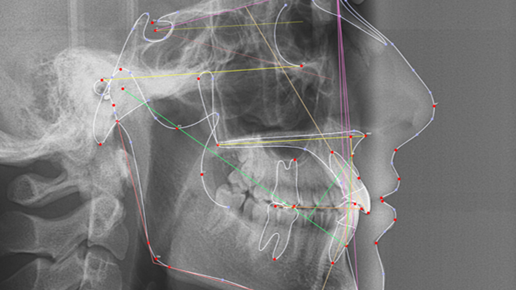

Диагностика перед ортодонтическим лечением. Что? Зачем? И для чего?

Здравствуйте, дорогие читатели! Сегодня мы расскажем Вам, что такое диагностика и для чего она нужна. Диагностика – это сбор и анализ данных пациента с целью составления грамотного плана лечения. Перед #ортодонтическим лечением важно собрать как можно больше информации о пациенте, все проанализировать и составить подробный план лечения, иначе можно получить совсем не тот результат, на который рассчитывали врач и пациент. Ортодонтия – это долгий путь, и он будет гораздо комфортнее, если вы заранее все предусмотрели...

Диагностика - важнейший инструмент в руках специалиста.

Всем привет! Сегодня хочу поговорить с вами о важности диагностики. Помните – когда вы приходите к врачу с какими-то жалобами, то сначала врач назначает вам обследования – сдать анализы, возможно пройти УЗИ, рентген, а в более серьезных случаях – КТ, МРТ. Для чего это делается? Конечно же для того, чтобы назначить ГРАМОТНОЕ лечение, иначе можно навредить организму и получить серьезные последствия. По статистике Минздрава из-за неверных действий врачей и неправильно подобранного лечения в России «гибнет» 70 тысяч человек в год (слово гибнет помещено в кавычки, т...